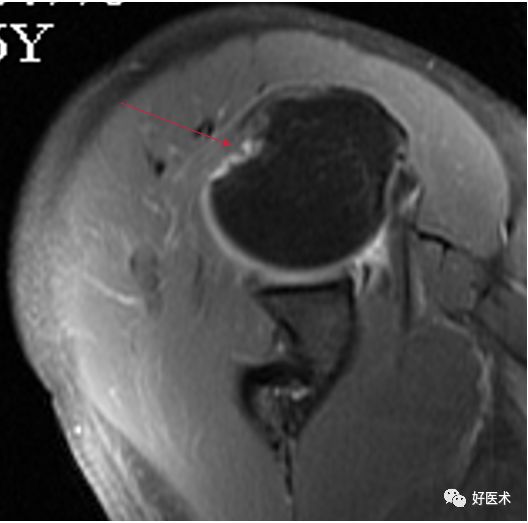

SLAP、Bankart合并Hill-Sach损伤

Hill-Sachs损伤

-

Hill-Sachs损伤:肩关节前脱位时,肱骨头撞向关节盂缘可导致肱骨头的后外侧的嵌插骨折

MR间接关节造影1.5T轴位T1W脂肪抑制